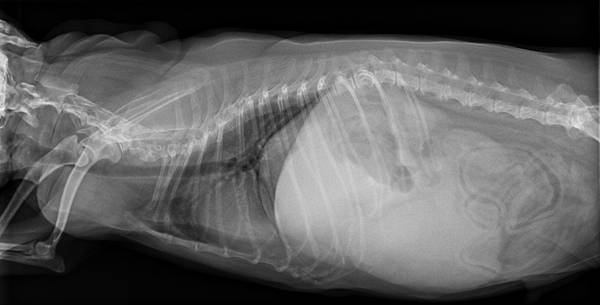

手術後X光